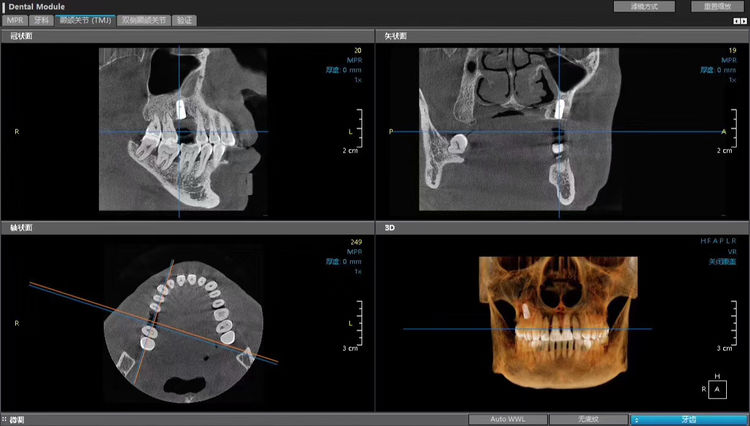

隨著口腔醫(yī)學(xué)種植技術(shù)的發(fā)展,慶陽市中醫(yī)醫(yī)院口腔科在醫(yī)院的大力支持下,先后引入國際先進水平的kavo齒科錐形束CT和日本NSK種植牙設(shè)備,并邀請第四軍醫(yī)大學(xué)口腔醫(yī)院種植外科主任蒞臨我科進行種植手術(shù),為廣大患者提供專業(yè)并便利的診療環(huán)境。

kavo齒科錐形束CT

三維分析

模擬種植牙數(shù)據(jù)

以上為人們對種植牙的常見問題解析,具體手術(shù)方案需至我院口腔科進行??茩z查,并在齒科CT上測量缺失牙的骨密度等數(shù)據(jù)?,F(xiàn)我科已開始進行種植手術(shù)預(yù)約,如需了解更多信息,請至慶陽市中醫(yī)醫(yī)院口腔科進行咨詢。